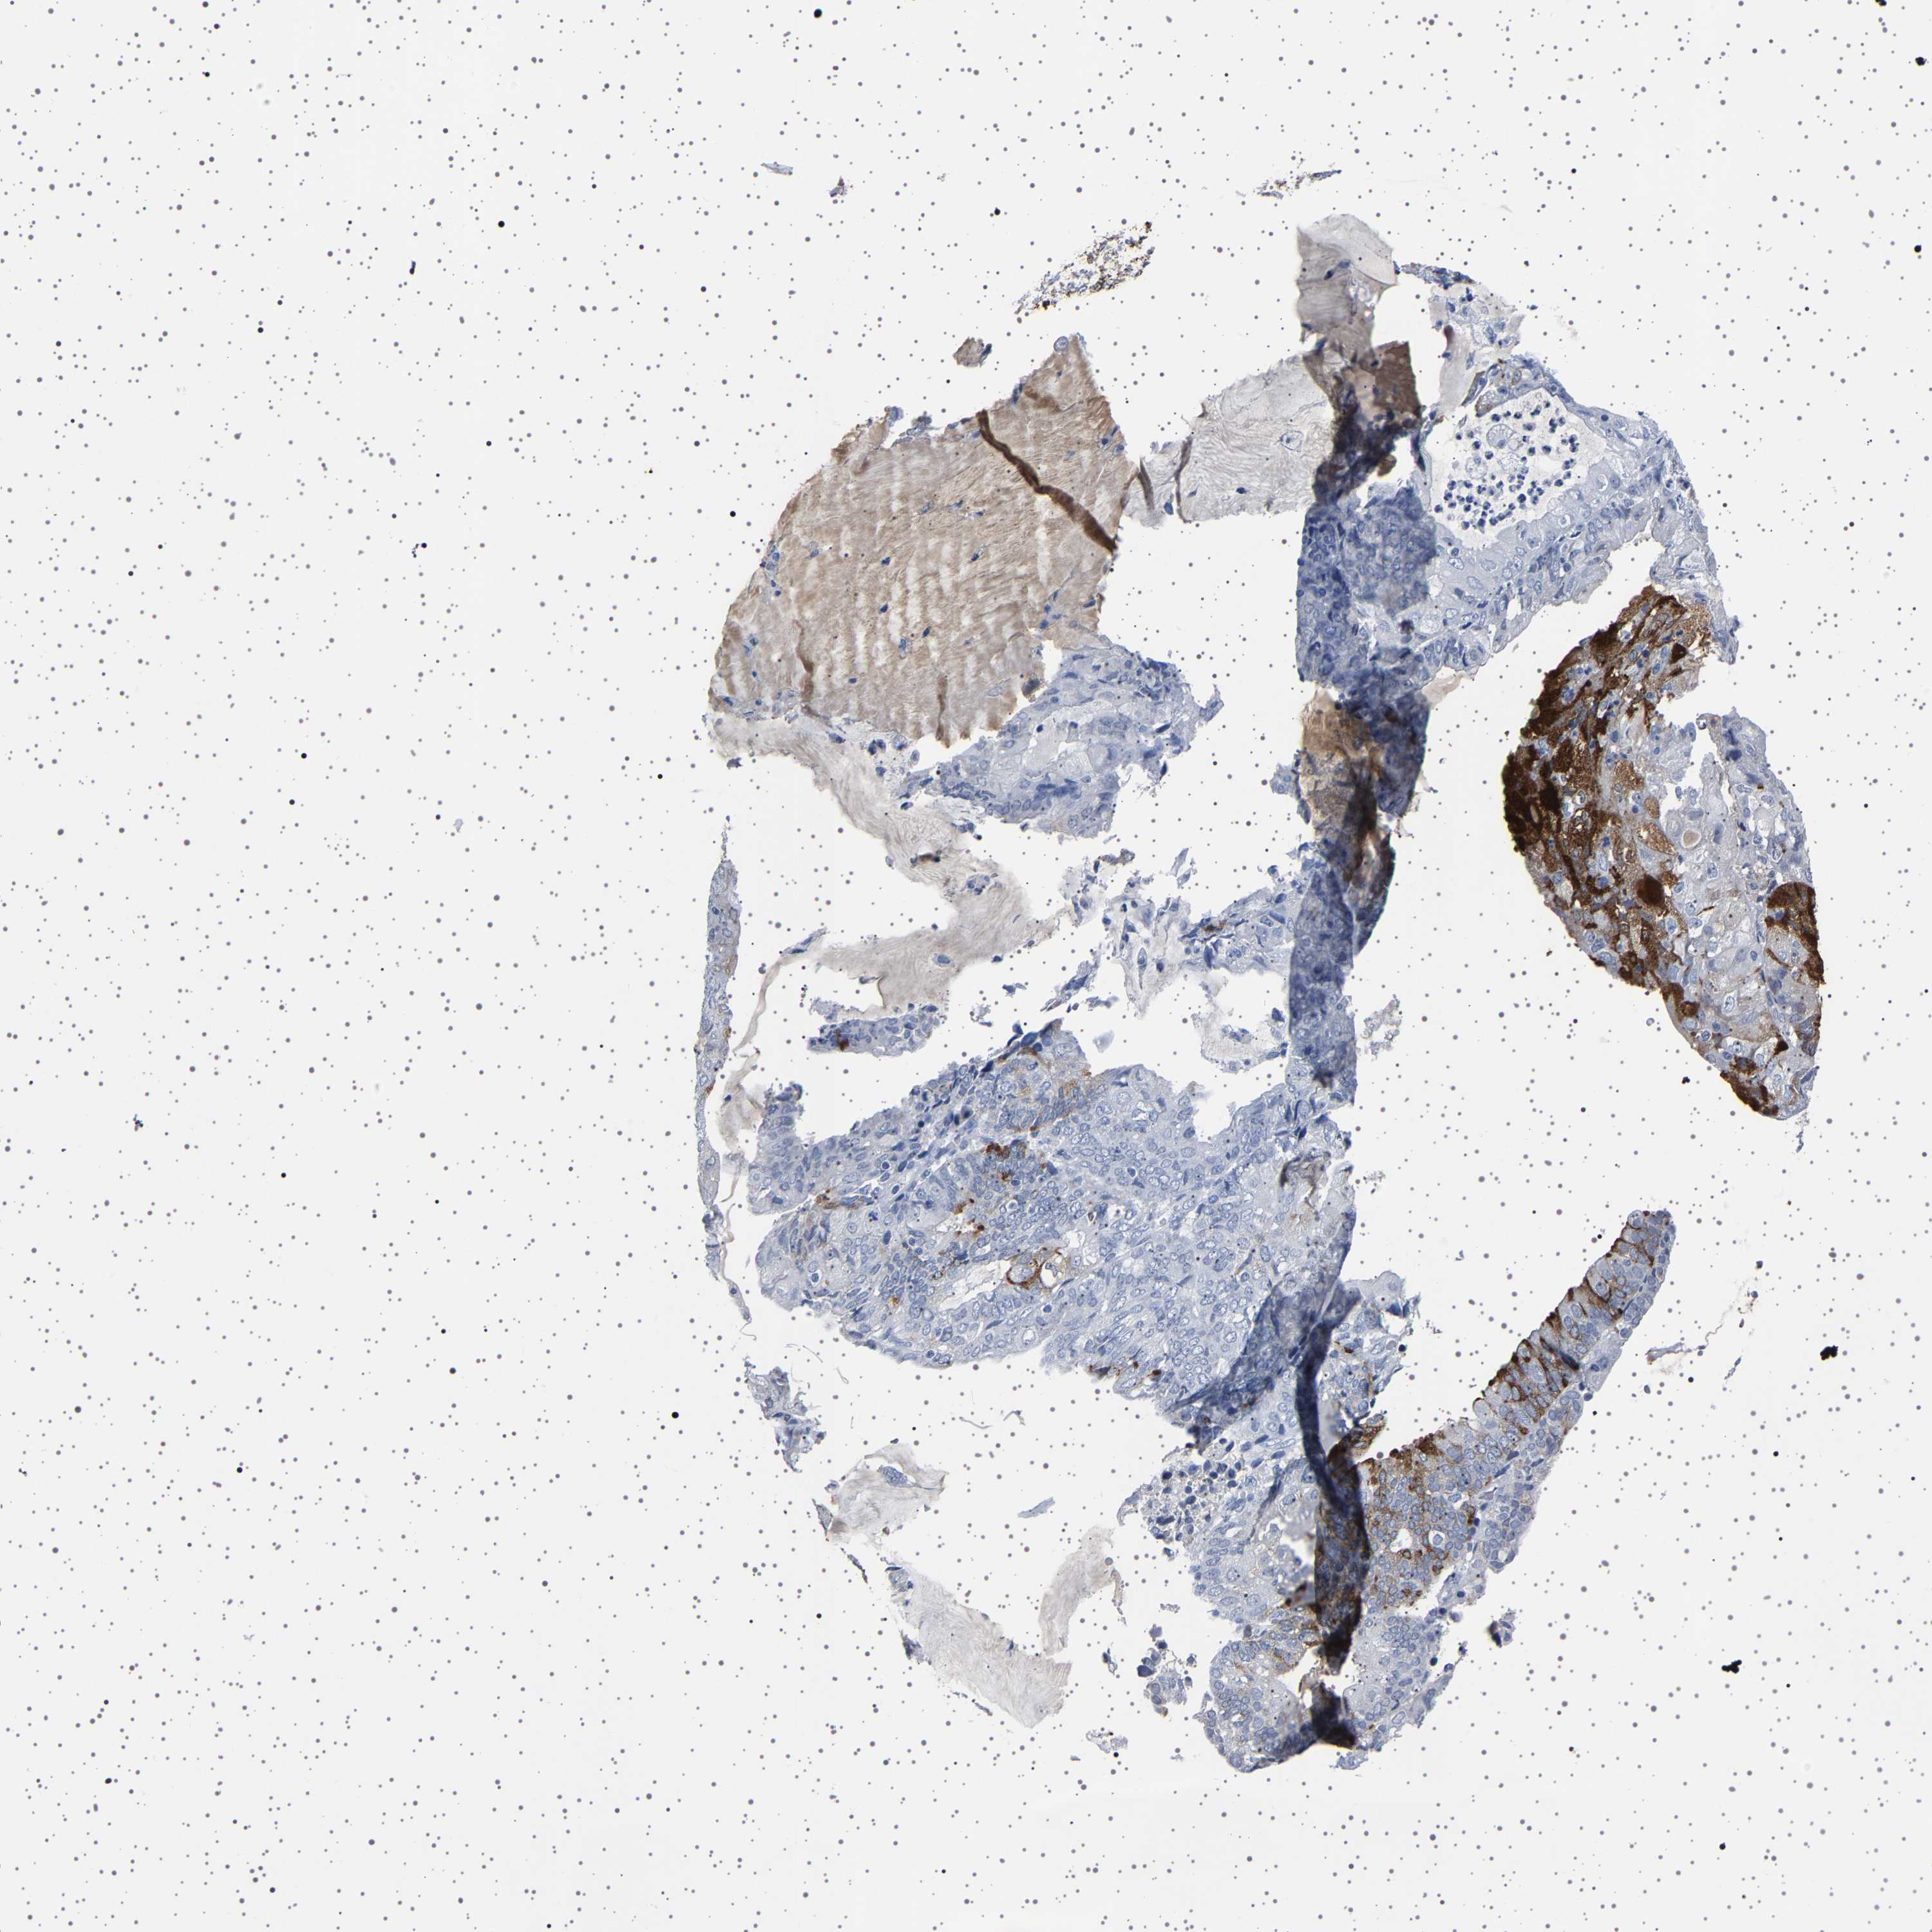

ENDOMETRIAL CANCER - Protein expressioni

A mouse-over function shows sample information and annotation data. Click on an image to view it in a full screen mode. Samples can be filtered based on level of antibody staining by selecting one or several of the following categories: high, medium, low and not detected. The assay and annotation is described here.

Note that samples used for immunohistochemistry by the Human Protein Atlas do not correspond to samples in the TCGA dataset.

Antibody stainingi

Antibody staining in the annotated cell types in the current human tissue is reported as not detected, low, medium, or high, based on conventional immunohistochemistry profiling in selected tissues. This score is based on the combination of the staining intensity and fraction of stained cells.

Each image is clickable and will lead to virtual microscopy that enables deeper exploration of all samples and also displays staining intensity scores, fraction scores and subcellular localization as well as patient and tissue information for each sample.

Antibody HPA035464

Antibody CAB020681

Staining

High

Medium

Low

Not detected

Intensity

Strong

Moderate

Weak

Negative

Quantity

>75%

75%-25%

<25%

None

Location

Nuclear

Cytoplasmic/membranous

Cytoplasmic/membranous,nuclear

Adenocarcinoma, metastatic, NOS